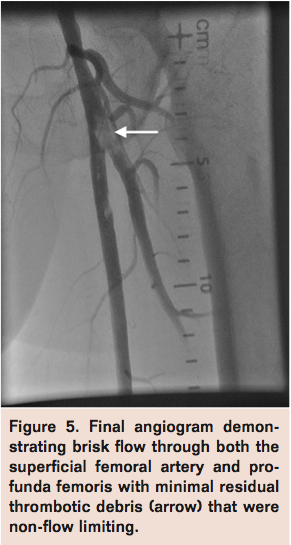

A 4 x 20 mm Sterling Balloon Dilatation Catheter (Boston Scientific) was then inflated distal to the thrombus in the PF and retrieved along with the guiding catheter to trap any embolic material between the balloon and the guide (Figure 2). Finally, the AngioJet catheter (Bayer HealthCare Radiology & Interventional) was advanced over the V-18 wire into the PF and SFA for rheolytic thrombectomy (Figure 3). Subsequent angiogram revealed moderate improvement in flow with persistent thrombotic material in both PF and SFA. A 6 x 100 mm Sterling Balloon Dilatation Catheter and a 4 x 30 mm Sterling Balloon Dilatation Catheter were then used to perform simultaneous kissing angioplasty of the SFA and PF respectively with good expansion (Figure 4). Final angiogram revealed significant improvement in flow through the SFA and PF segments with minimal residual thrombotic debris that were non-flow limiting (Figure 5). The patient was noted to have clinical reperfusion of his left lower extremity with resolution of symptoms, and he was discharged on hospital day 17 with a 6-week course of intravenous antibiotics.